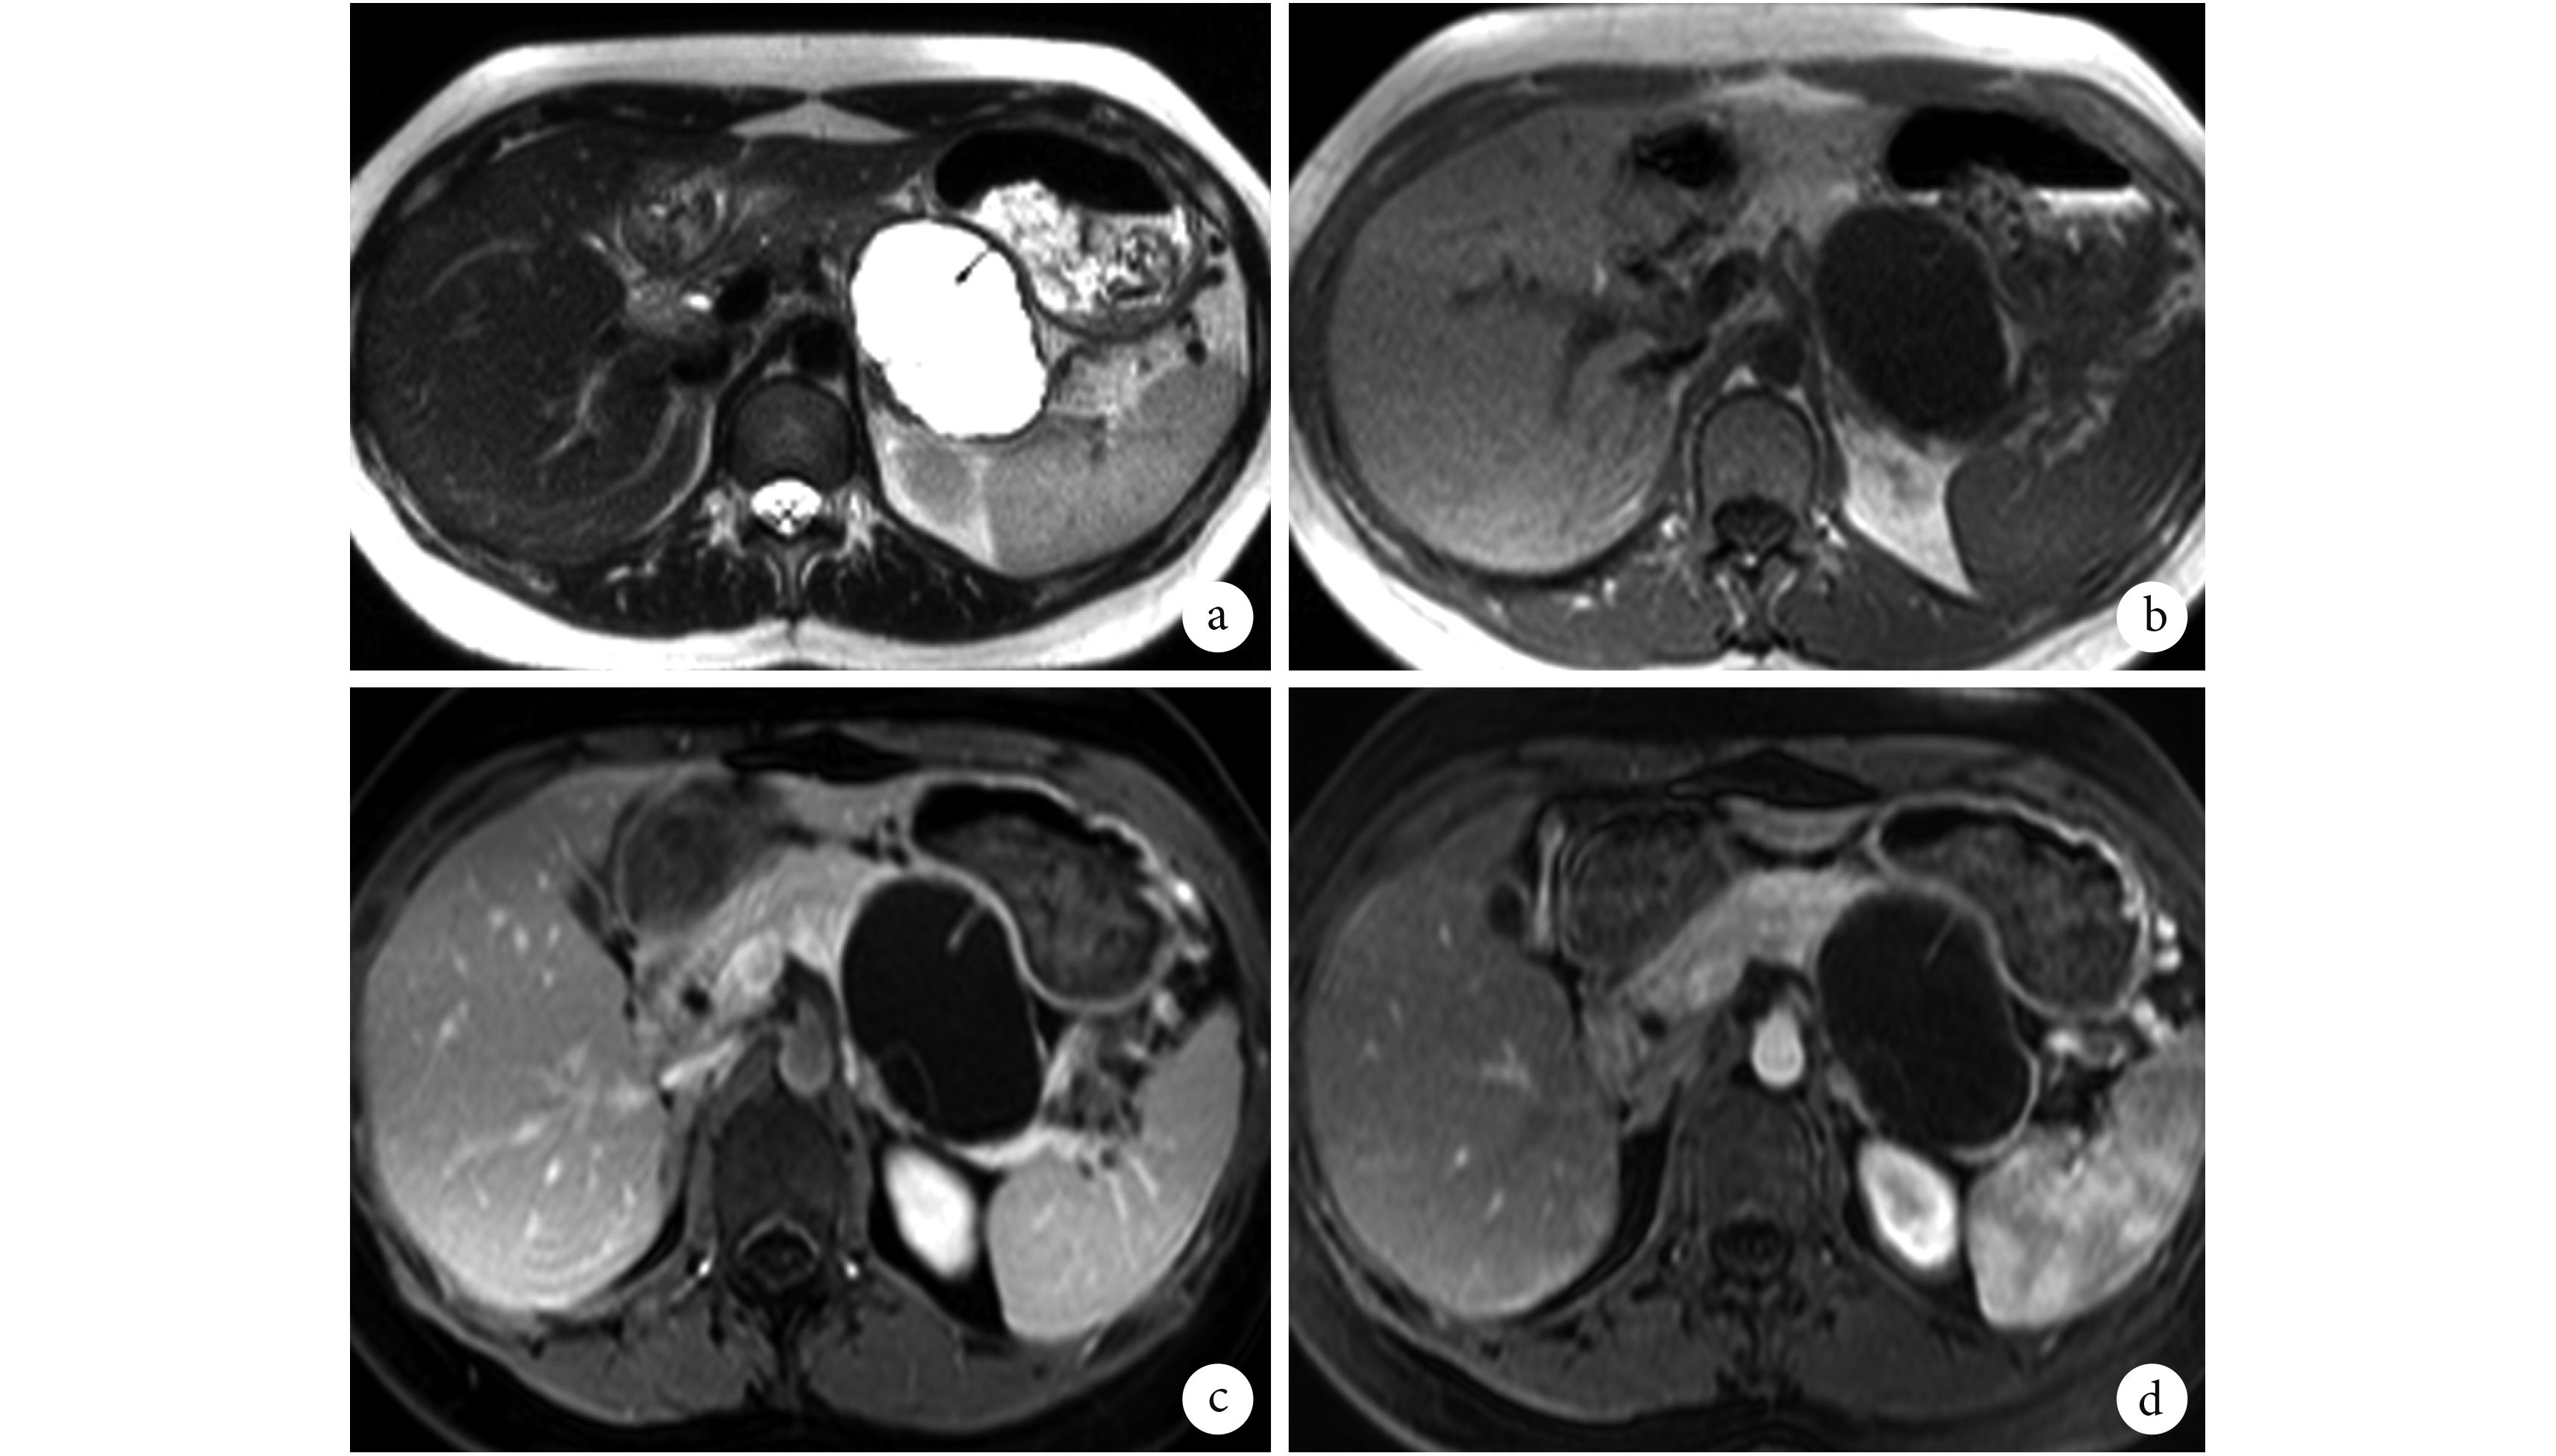

本組10例SPTP病例中,6 例行CT檢查、3 例行MRI檢查,1 例同時行CT和MRI檢查。腫瘤位于胰頭部 1 例,體胰尾部 9 例;腫瘤直徑2.3~13 cm,平均5.3 cm;呈圓形或類圓形 7 例,分葉狀 3 例;7 例見完整包膜、2 例包膜欠連續、1 例未見包膜。在CT或MRI平掃圖像上,2 例實性成分為主的SPTP表現為邊界清楚、密度(信號)稍欠均勻的軟組織密度(信號)腫塊,囊性成分主要位于腫塊中心;5 例囊實性成分相仿的SPTP表現為軟組織與液性密度(信號)混雜的腫塊,囊實性成分分界欠清;3 例囊性成分為主的SPTP表現為液性密度(信號)為主的混雜密度(信號)腫塊,實性成分位于腫瘤邊緣呈“壁結節”樣改變,或散在分布于腫瘤內呈“浮云征”樣改變。3 例(實性腫瘤 1 例,囊實性成分相仿腫瘤 2 例)MRI圖像所顯示腫瘤內出血獲手術病理證實(圖 2),1 例實性成分為主腫瘤CT平掃顯示腫瘤內散在分布小點狀鈣化。在CT、MRI多期動態增強掃描圖像上,所有病例腫瘤實性成分及包膜均表現為動脈期輕度強化、靜脈期及延遲期漸進性強化模式,其中 9 例在延遲期強化程度低于正常胰腺實質、1 例延遲期強化程度與正常胰腺實質相近,囊性成分各期均不強化,增強掃描后囊、實性成分分界趨于清楚。1 例位于胰頭部的SPTP壓迫膽總管壺腹部且與十二指腸環分界不清,肝內、外膽管及主胰管擴張,膽囊增大。

SPTP的起源目前尚有爭議,有認為起源于胰腺外分泌腺細胞、內分泌腺細胞或具有向內外分泌腺分化的全能細胞等。它是一種良性、交界性或低度惡性的腫瘤,約占胰腺所有腫瘤的0.9%~2.7%[7]。體尾部多見,年輕女性好發,男女發病比例約1∶8,腫瘤常較大,平均直徑可達7.8 cm[8],本組病例5.3 cm。SPTP在CT或MRI上的表現依據腫瘤囊實性成分的比例及分布差異呈現不同的影像特點:以囊性成分為主者實性成分常位于腫瘤邊緣或散在分布于腫瘤內呈“壁結節”或“浮云征”表現[9];囊實性成分相仿者囊實性結構常相間分布;以實性成分為主者囊性成分多位于包膜下或散在分布于實性成分中。CT及MRI動態增強掃描對SPTP與其他胰腺腫瘤相鑒別具有重要價值:SPTP實性成分常表現為漸進性強化且強化程度一般低于正常胰腺實質、少數延遲期強化程度可接近正常胰腺實質[10],囊性成分不強化,強化后囊實性成分分界清楚。本組10例增強掃描均表現為漸進性強化特點,其中 9 例強化程度低于正常胰腺,1 例延遲期強化程度與正常胰腺實質接近。SPTP容易并發出血[11-12],當T1W平掃圖像上腫瘤內出現高信號或出現液-液平常提示出血[9,13-14],本組 3 例腫瘤出現上述征象經手術及病理學檢查證實瘤內有出血。鈣化是SPTP的另一常見影像學特征[15],鈣化多位于腫塊邊緣,呈點狀或細條狀,甚至可表現為殼狀鈣化,CT平掃顯示鈣化敏感,本組 1 例發現散在點狀鈣化灶。SPTP常具有完整的包膜,對周圍組織常表現為壓迫征象,即使位于胰頭部也不易引起肝內外膽管及主胰管擴張[16];少數腫瘤出現局部包膜不連續、腫瘤與鄰近結構分界不清或出現鄰近血管被包繞,可提示腫瘤有惡性傾向,本組 2 例有此征象并獲手術及病理學檢查證實。